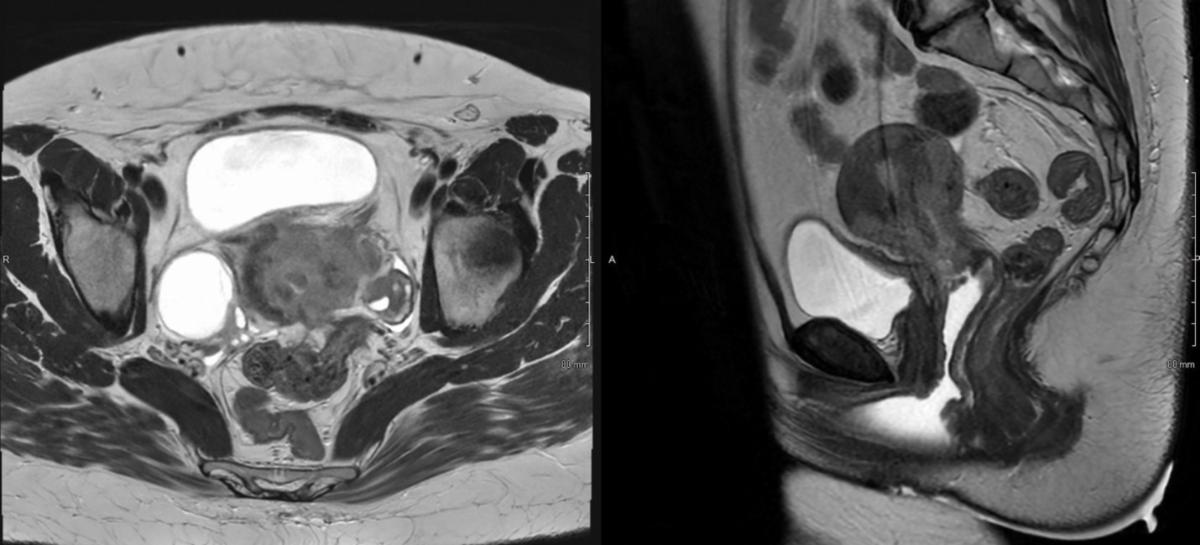

A 38-year-old woman with 1 year history of menometrorrhagia and prior abnormal Pap was found to have FIGO stage IIB moderately-differentiated, HPV-associated, cervical squamous cell carcinoma. Her disease had extensive involvement of the myometrium, parametria, and vagina without nodal involvement (Figures 1A-B). On speculum exam, the cervix was flush with the upper vagina and replaced by friable, irregular, tissue with a visible os. Bimanual exam demonstrated a 5 cm cervical mass with extension to the anterior and left vaginal fornices, and left parametrial extension on rectovaginal exam.

Given the extent of disease, she was recommended and ultimately treated with definitive external-beam radiotherapy (EBRT) and concurrent weekly cisplatin (40 mg/m2 IV) followed by four fractions of high-dose-rate (HDR) cervical brachytherapy. EBRT was delivered to the pelvis and at regional nodes to 45 Gy, followed by HDR brachytherapy, 4 fractions of 7 Gy each to the cervical high-risk clinical tumor volume (HR-CTV), delivered twice-weekly. Serial exams during EBRT showed early response. Repeat pelvic MRI in week 4 confirmed tumor response but with residual disease (Figure 2).

Figure 1B – pre-treatment Pelvic MRI, T2 sequence

Figure 2 – mid-treatment Pelvic MRI, T2 sequence